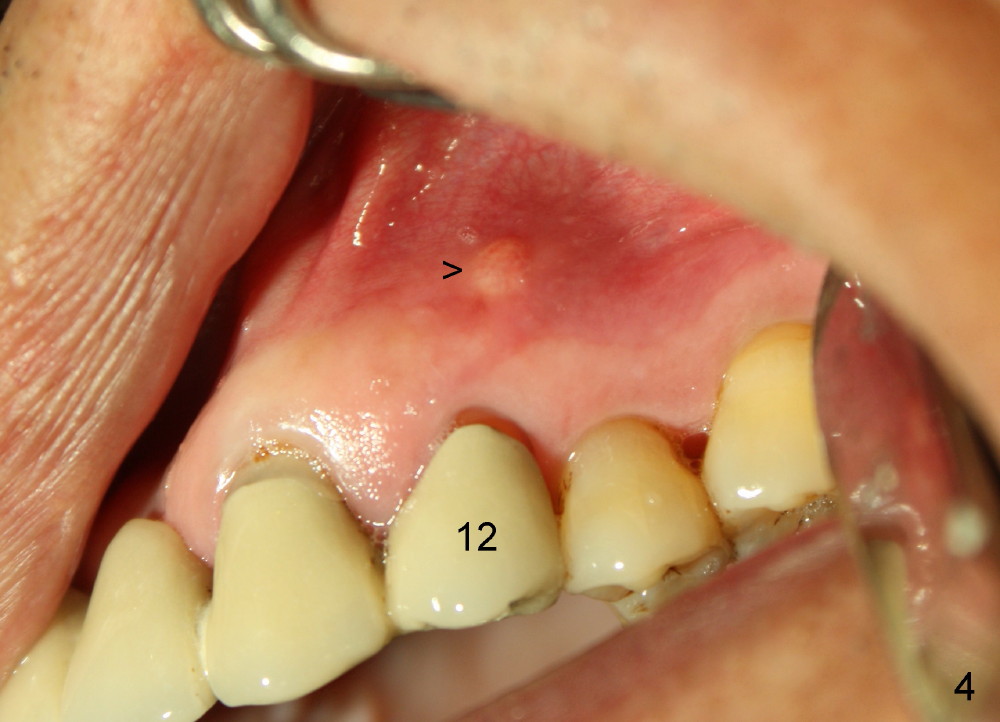

One month later, the fistula is regressing, while the pain reduces (Fig.4). It appears that the initial access is not extended lingually enough (Fig.5). The lingual canal is still non-negotiable when the access is enlarged (Fig.6). Working length of the buccal canal is confirmed with 30/.06 Gutta Percha in place (Fig.7). After explanation and consent, RCT is finished routinely. Two months postop, the buccal apical fistula resolves with no symptom (Fig.8). The retainer at the site of #12 is not removed to increase chance of finding the missing canal. It is part of a long bridge.